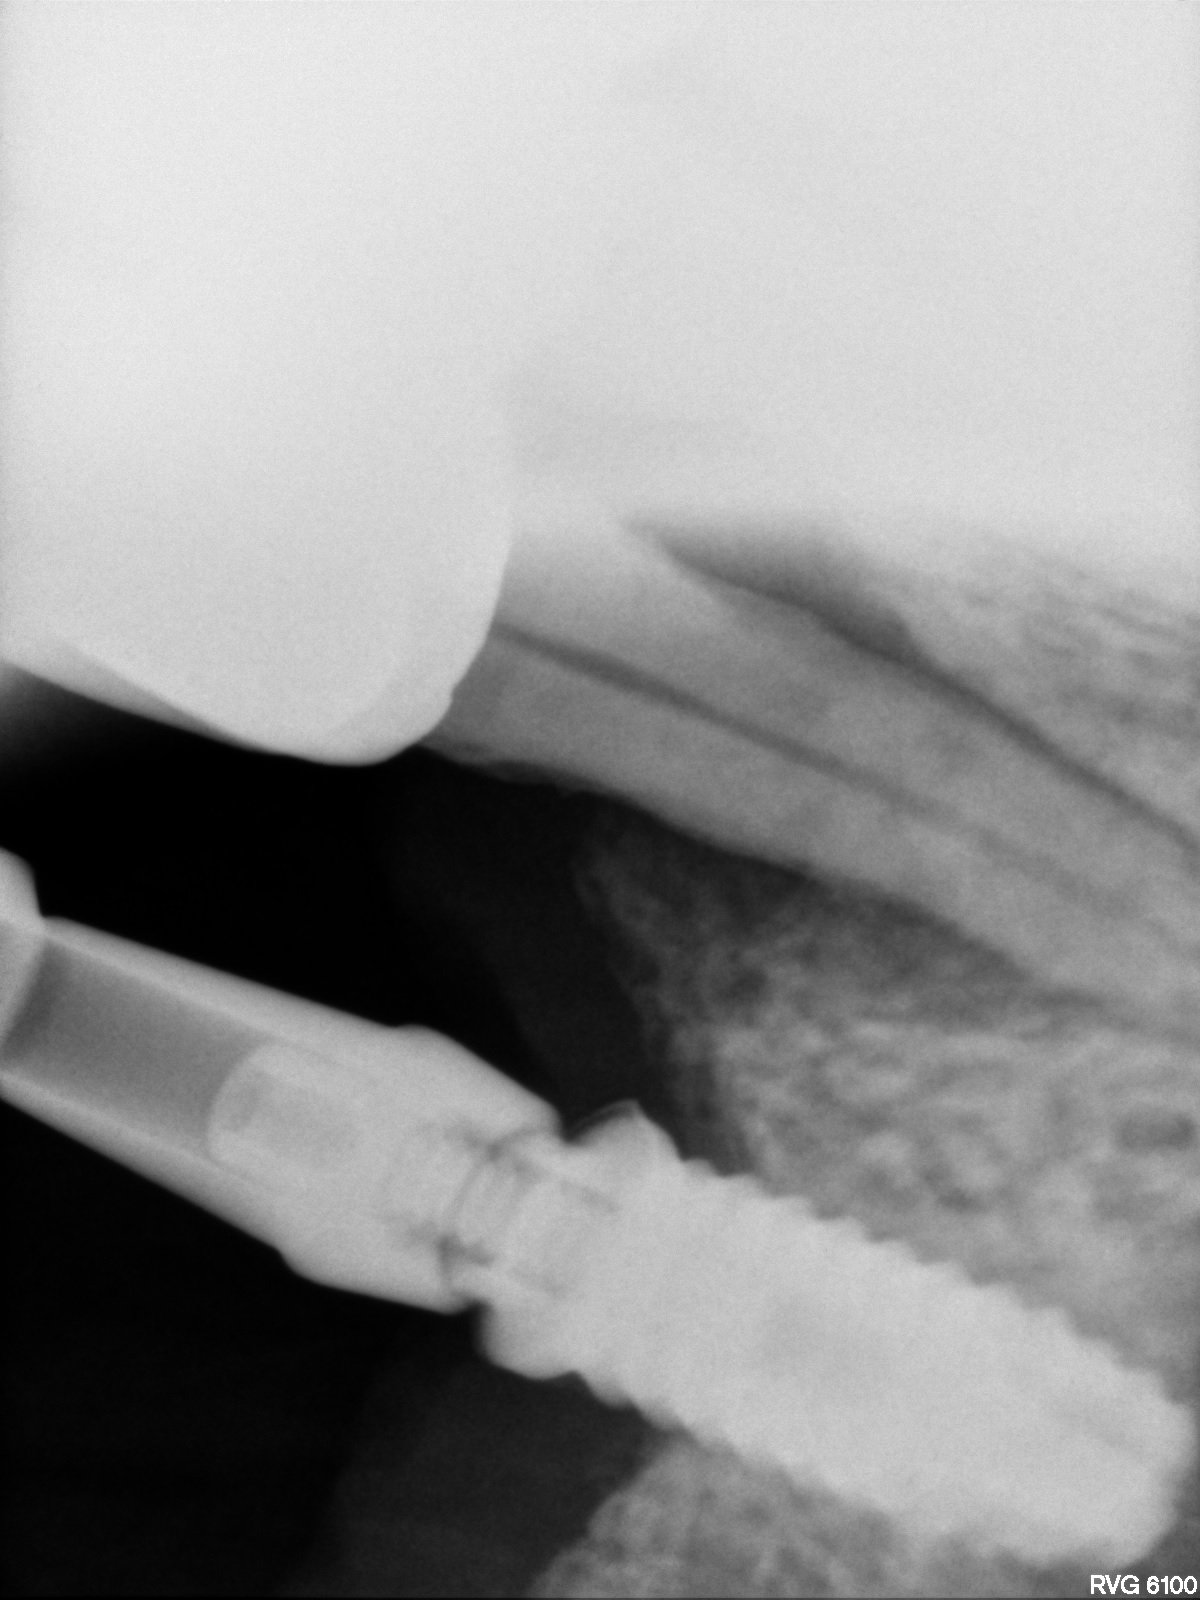

Buenas! Quería saber qué implante tiene la paciente en posición #14 y qué tipo de pilar lleva. Parece que es un pilar para cementar y fresaron la cabeza del tornillo [...]